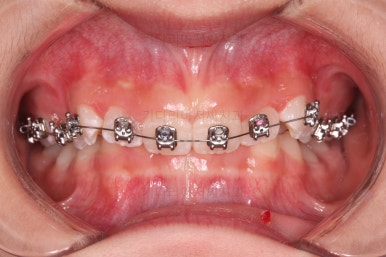

우선 윗니에만 교정장치를 부착했습니다.

성장치료라더니 교정치료? 하실 수 있지만 윗니를 가지런하게 해준 이유는 아래턱을 앞으로 성장시켜줄려니 윗니 앞니가 옥니처럼 가로막고 있어서 아래턱이 앞으로 나올래야 나올 수 없는 상황이었어요.

그래서 앞니의 각도를 먼저 개선해주기로 했죠.

일반적인 교정장치이긴 하지만 그 목적이 달랐던 거에요.

앞니의 각도가 앞으로 살아난 것이 보이실 거에요.

자연스럽게 과개교합 경향도 개선되어 어금니로 물었을 때 아래 앞니가 점점 보이기 시작하네요.